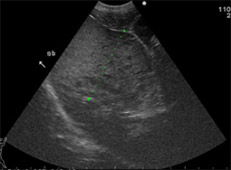

病名:褐色細胞腫 手術法:右副腎腫瘍摘出術

症例:9歳 Mix犬 避妊雌

主訴:1ヶ月前から急に元気がなくなり、失神することもあるとのことでかかりつけの病院で診察をうけ、検査にて腹腔内に腫瘍があるとのことでご紹介を受け当病院に来院されました。

腹部超音波検査およびCT検査にて右副腎に直径6cm大の腫瘍(赤矢印)が認められました。機能性副腎腫瘍が疑われ、飼い主様の希望により摘出手術を行いました。